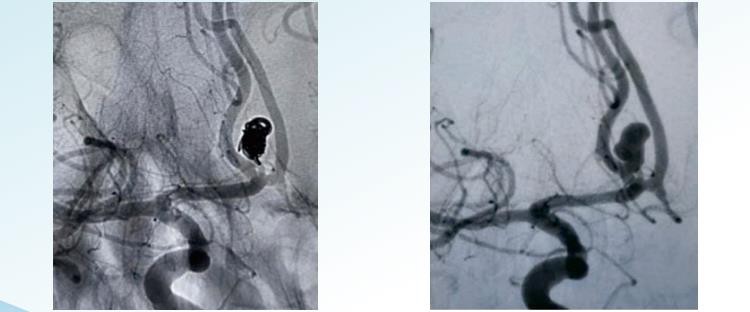

RenovaTM3D eemaldatavad mähised

RenovaTMSpiraalsed eemaldatavad mähised